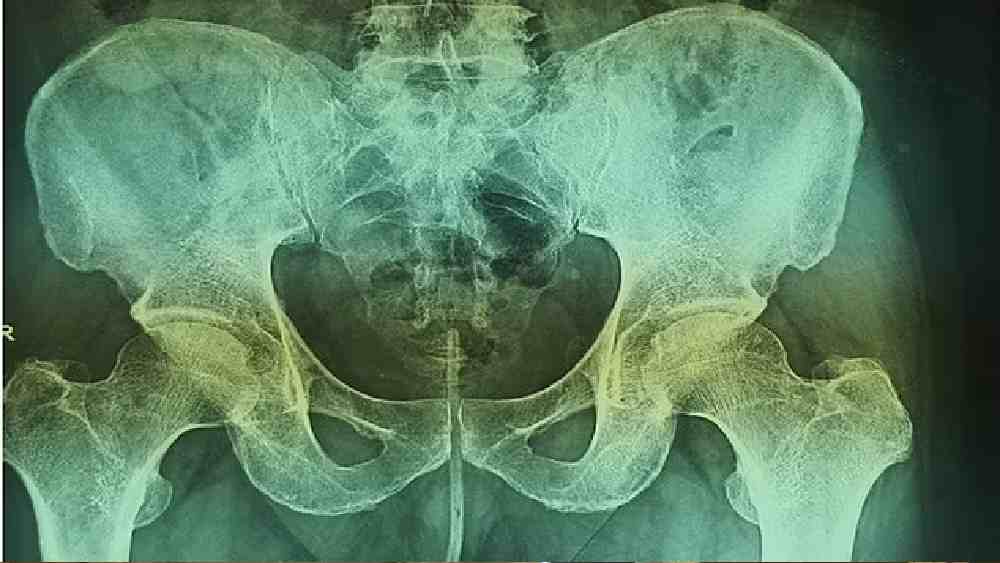

ওই ব্যক্তির এক্স-রে।

ওই ব্যক্তির এক্স-রে। ছবি: সংগৃহীত

এক্স-রে পরীক্ষায় ধরা পড়ে, তারটি মূত্রনালি ছাড়িয়ে ওই বৃদ্ধের মূত্রথলি পর্যন্ত পৌঁছে গিয়েছে। প্রাথমিক ভাবে অস্ত্রোপচারের কথা ভাবলেও পরে চিকিৎসকরা চিমটা দিয়ে টেনেই তারটি বার করার সিদ্ধান্ত নেন। কিন্তু যে বিষয়টি দেখে চিকিৎসকরা চমকে যান, সেটি হল এত কিছুর পরেও কোনও ধরনের ক্ষত দেখা যায়নি ওই বৃদ্ধের যৌনাঙ্গে। হয়নি কোনও ধরনের রক্তপাতও। তবে গোটা বিষয়টি নিয়েই তাঁরা দিয়েছেন সতর্কতার বার্তা। চিকিৎসকরা জানাচ্ছেন, এই ধরনের কাজ গুরুতর ক্ষতি করতে পারে মূত্রনালির, ছিদ্র হয়ে যেতে পারে মূত্রথলি। বেড়ে যায় মূত্রনালিতে গুরুতর সংক্রমণের আশঙ্কাও। তাই মূত্র ত্যাগের সমস্যায় এই ধরনের কাজ একেবারেই অনভিপ্রেত বলে মত তাঁদের।